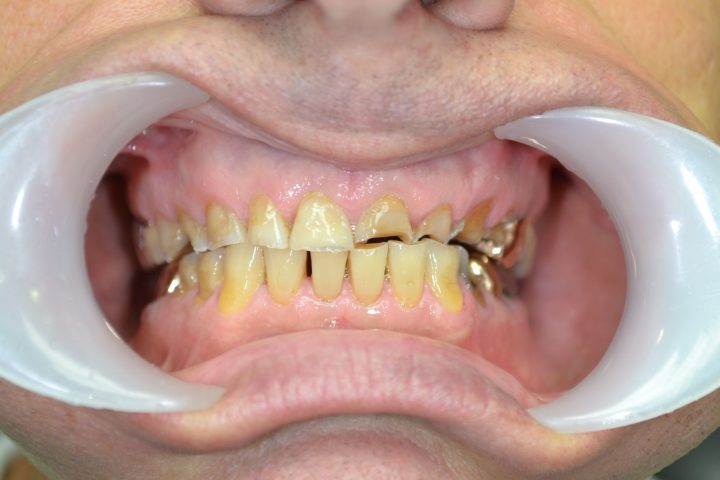

Chris

Chris ist ein 31-jähriger Engländer. Wegen dem unsystematischen Lebensstil und der nachlässigen Zahnreinigungsgewohnheit sind ein paar Zähne bis seinem 30. Geburtstag übrig, und sind in rettungslosem Zustand.

Als er die Klinik besucht hat, konnte nicht mehr essen, weil er immer unter Kieferschmerzen gelitten hat. Aufgrund von der CT-Aufnahme hat Frau. Dr. Erdélyi den Behandlungsplan erstellt. Die übrigen Zähne wurden aus dem Grund von einer großen Entzündung entfernen.

In der gleichen Behandlung hat er noch oben 4, und unten 6 Implantate bekommen, daneben hat er im Ablauf den 5 Tagen provisorischen Zahnersatz gekriegt.

Danach hatte er 4 Monate lange Heilungszeit, bald war den endgültigen Zahnersatz fertig: Oben wird eine Stegprothese auf 4 Implantate bearbeitet, unten wird eine Brücke auf 6 Implantate befestigt.